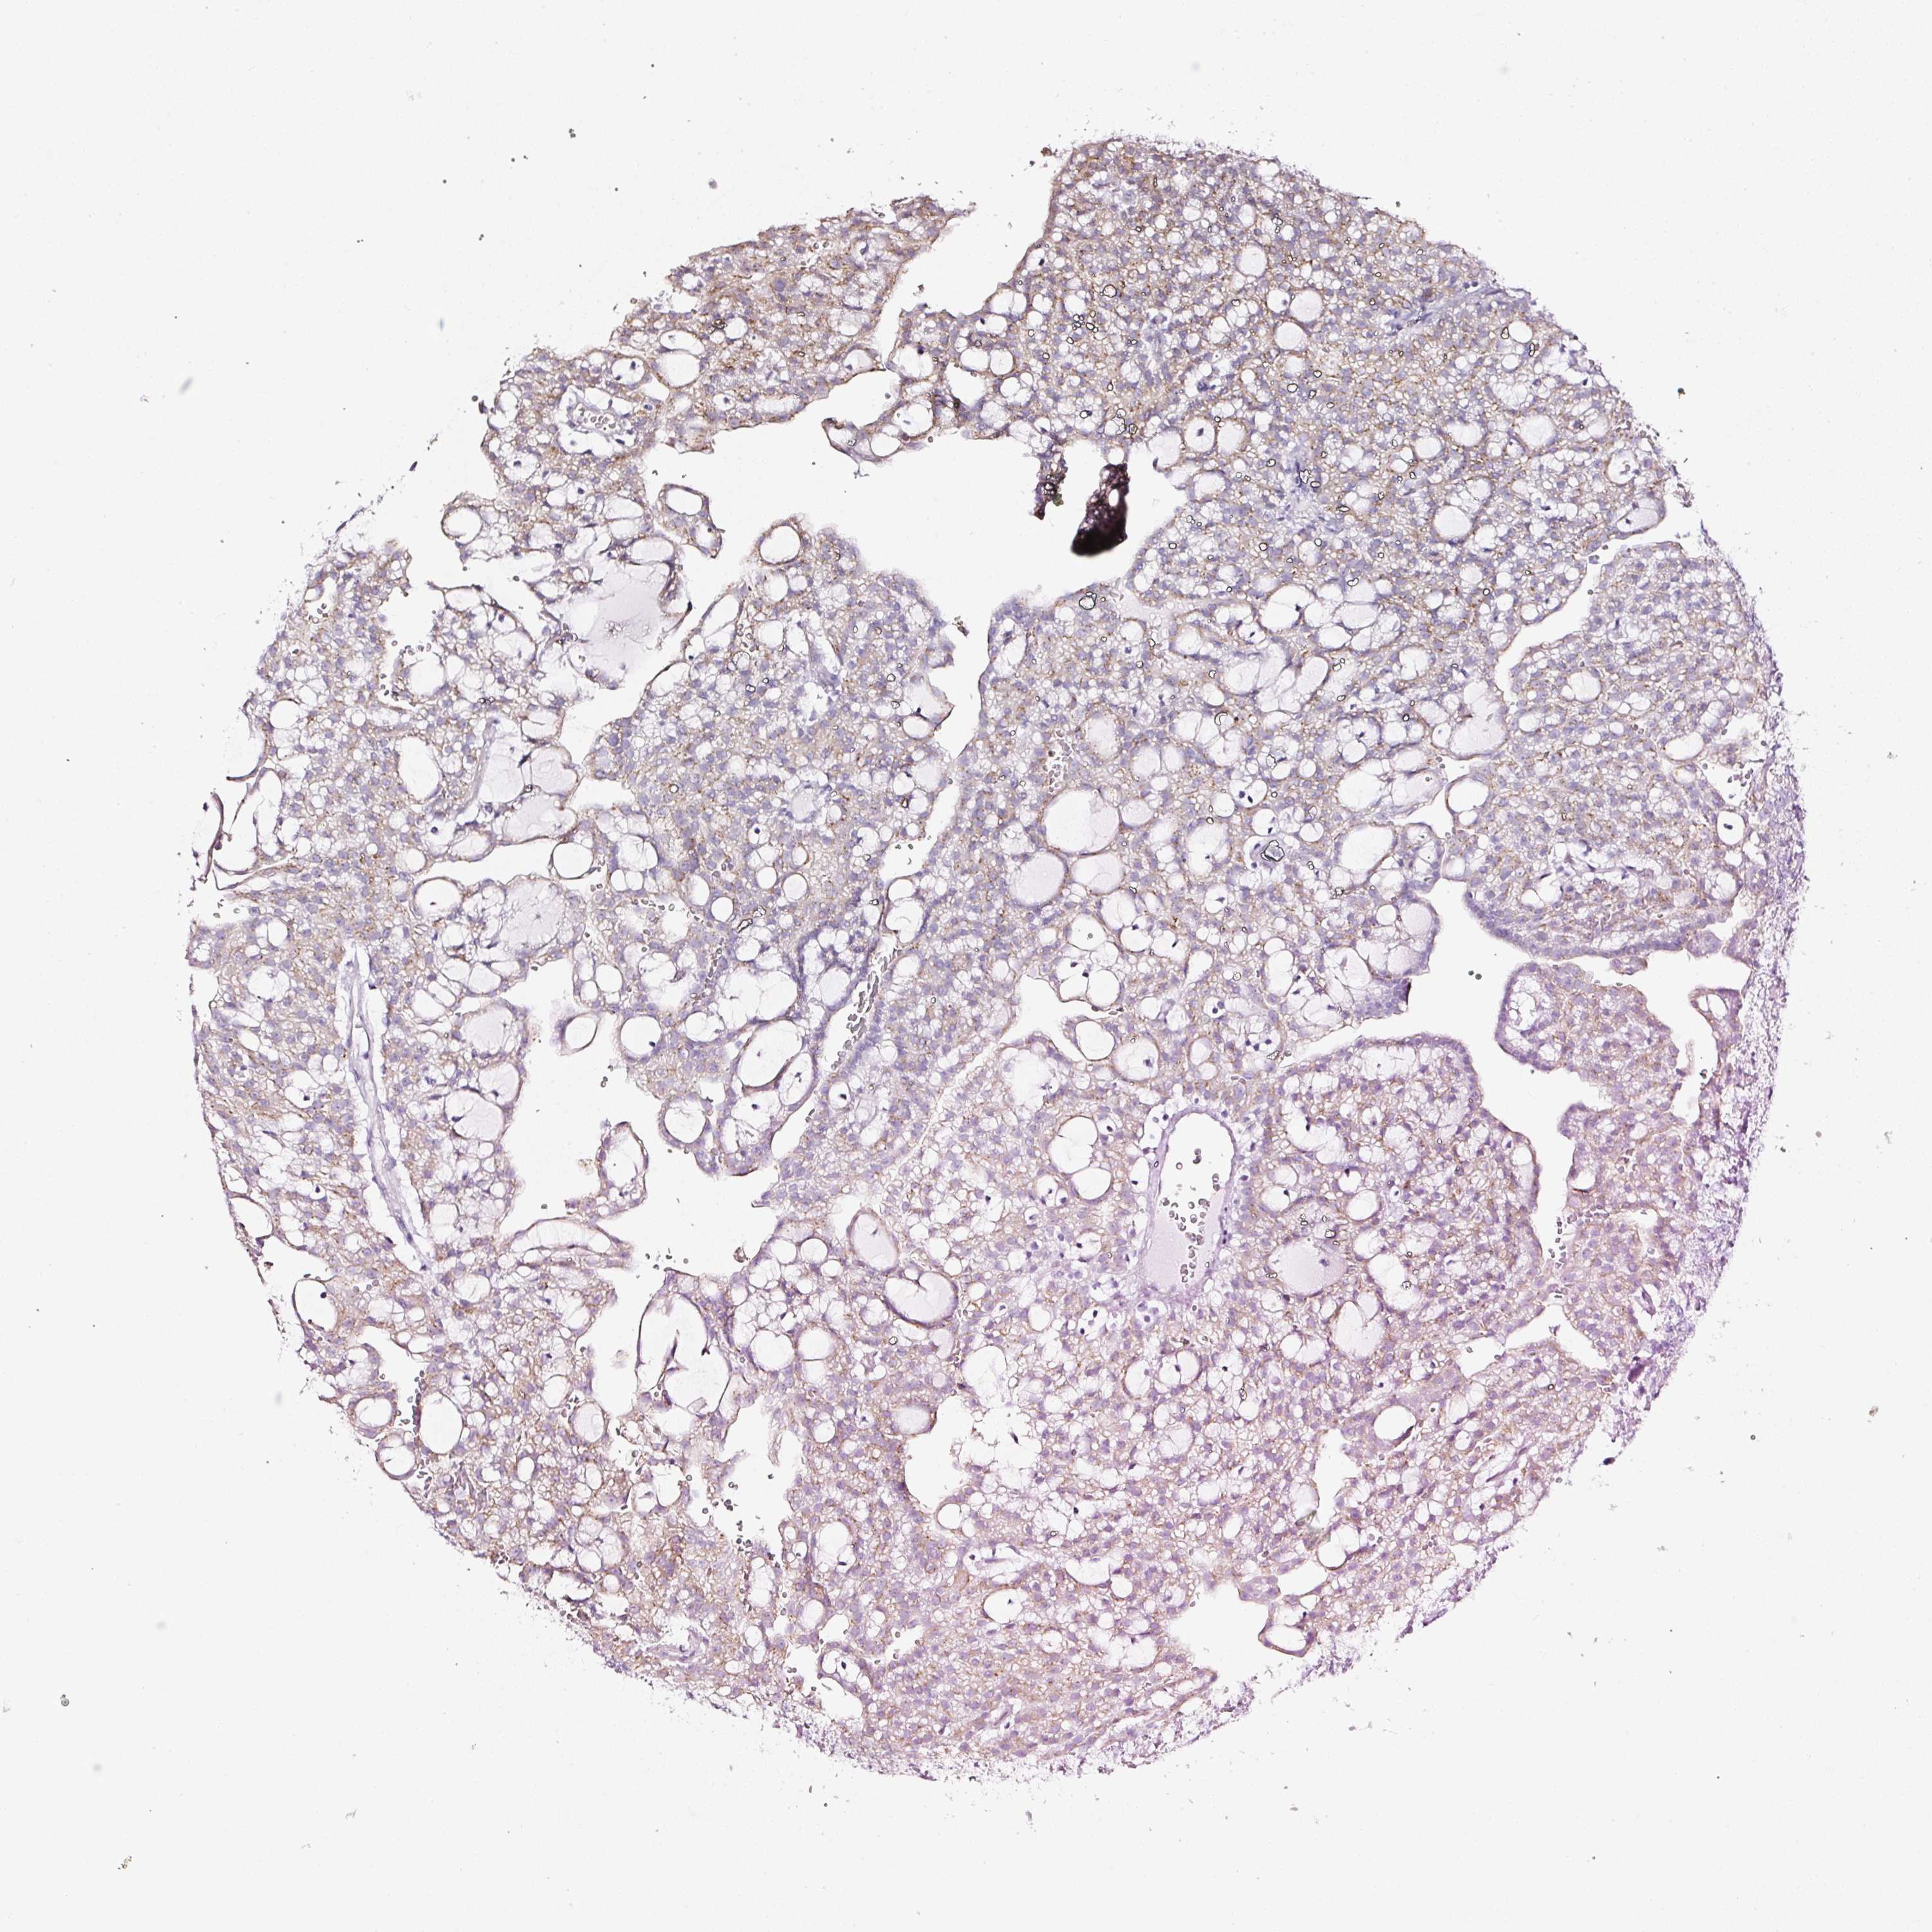

KIDNEY RENAL CLEAR CELL CARCINOMA (TCGA) - Interactive survival scatter ploti

The Survival Scatter plot shows the clinical status (i.e. dead or alive) for all individuals in the patient cohort, based on the same data that underlies the corresponding Kaplan-Meier plots. Patients that are alive at last time for follow-up are shown in blue and patients who have died during the study are shown in red.

The x-axis shows the expression levels (FPKM) of the investigated gene in the tumor tissue at the time of diagnosis. The y-axis shows the follow-up time after diagnosis (years). Both axes are complimented with kernel density curves demonstrating the data density over the axes. The top density plot shows the expression levels (FPKM) distribution among dead (red) and alive patients (blue). The right density plot shows the data density of the survived years of dead patients with high and low expression levels respectively, stratified using the cutoff indicated by the vertical dashed line through the Survival Scatter plot. This cutoff is automatically defined based on the FPKM cutoff that minimizes the p-score. The cutoff can be changed by dragging the vertical line or by entering a cutoff value in the square labeled "Current cut-off".

Under the Survival Scatter plot the p-score landscape (black curve; left axis) is shown together with dead median separation (red curve; right axis). Dead median separation is the difference in median mRNA expression between patients who have died with high and low expression, respectively. It is calculated as follows: median FPKM expression of dead patients with high expression - median FPKM expression of dead patients with low expression. This is intended to aid the user in visually exploring custom cutoffs and the associated p-scores and dead median separation.

Individual patient data is displayed and can be filtered by clicking on one or more of the category buttons on the top of the page. Categories describing expression level and patient information include: high, low, alive, dead, female, male and tumor stages. The scale of the x-axis can be toggled between linear and log-scale by clicking on the "x log" button. Mouse-over function shows TCGA ID, patient information and mRNA expression (FPKM) for each patient.

& Survival analysisi

Kaplan-Meier plots summarize results from analysis of correlation between mRNA expression level and patient survival. Patients were divided based on level of expression into one of the two groups "low" (under cut off) or "high" (over cut off). X-axis shows time for survival (years) and y-axis shows the probability of survival, where 1.0 corresponds to 100 percent.

SDF4 is potential prognostic, high expression is favorable in Kidney Renal Clear Cell Carcinoma (TCGA)

Best expression cut offi

Based on the FPKM value of each gene, patients were classified into two groups and association between prognosis (survival) and gene expression (FPKM) was examined. The best expression cut-off refers the FPKM value that yields maximal difference with regard to survival between the two groups at the lowest log-rank P-value. Best expression cut-off was selected based on survival analysis .

When clicking on this number, the vertical dashed line indicating cut-off, the interactive survival plot, and the Kaplan-Meier curve will be adjusted to show results based on the best expression cut-off.

: 106.12

P scorei

Log-rank P value for Kaplan-Meier plot showing results from analysis of correlation between mRNA expression level and patient survival.

N/A

Average pTPM 142.1

Number of samples 521